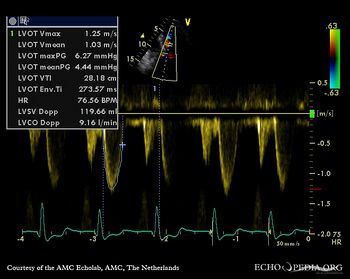

| Continuous-wave Doppler signal of transaortic flow | Pulsed-wave signal of flow in LVOT |